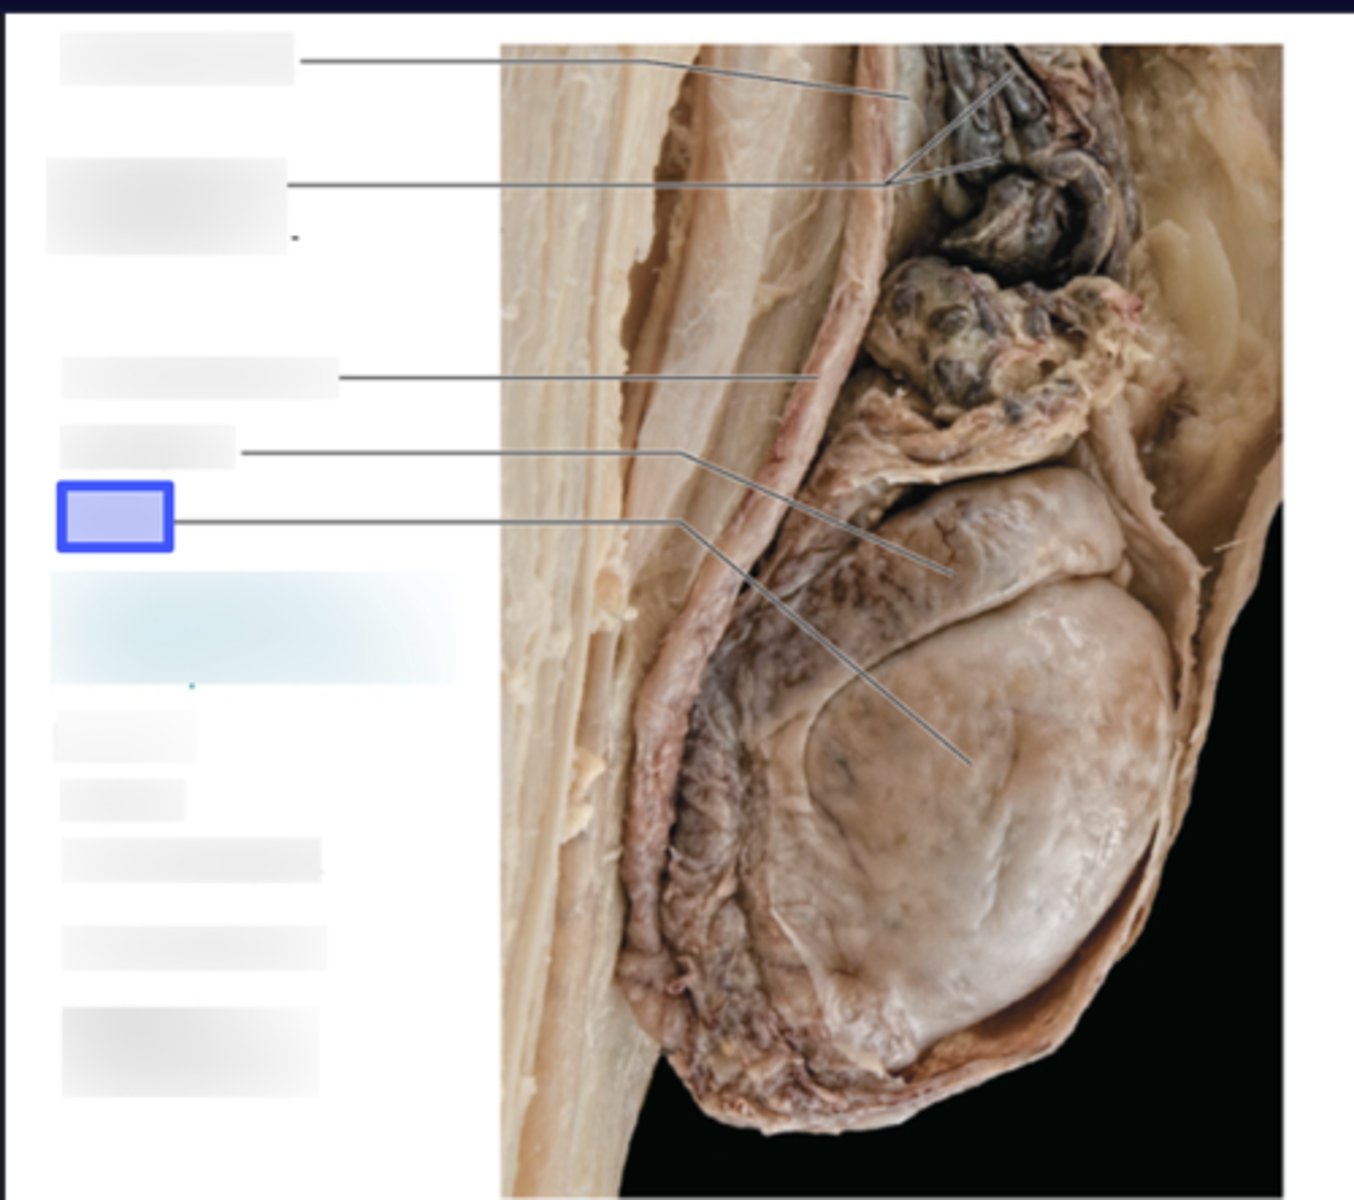

Diaphragm

Right Lobe of Liver

Left Lobe of Liver

Falciform Ligament

Ligamentum Teres

Gall Bladder

Cardia

Fundus

Body

Pylorus

Pyloric Sphincter

Gastric Rugae

Greater Curvature

Lesser Curvature

Greater Omentum

Lesser Omentum